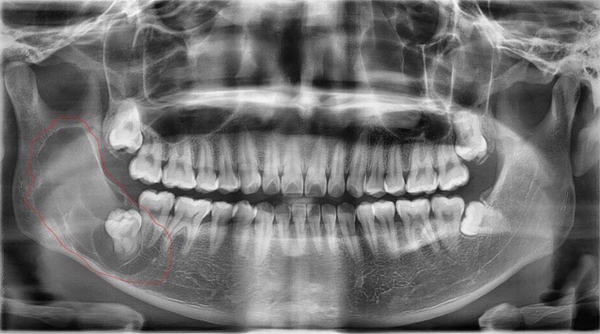

Thời gian gần đây, nam thanh niên thường xuyên thấy đau góc hàm bên phải, nghĩ rằng mình mọc “răng khôn”. Tuy nhiên khi thăm khám trên lâm sàng, bác sĩ không phát hiện bất thường nên chỉ định cho bệnh nhân chụp X-quang.

| Hình ảnh chụp X-quang cho thấy bệnh nhân có năng răng sừng hoá rất to ở góc hàm phải kèm theo 1 răng số 8 đâm ngang phía đối diện |

Kết quả cho thấy, bệnh nhân bị nang răng sừng hoá (hay còn gọi nang răng sinh sừng). Trường hợp bệnh nhân này nang rất lớn, phát triển từ răng số 7 lan lên tới tận xương hàm trên.

Ngày 4/6, BS Thái trực tiếp phẫu thuật cắt bỏ toàn bộ khối nang cho bệnh nhân, kích thước hơn 5 cm. Hiện tại, sức khoẻ bệnh nhân đã ổn định.